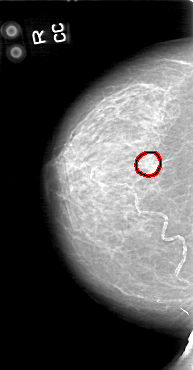

FILE: D_4044_1.RIGHT_CC.OVERLAY

TOTAL_ABNORMALITIES 1

ABNORMALITY 1

LESION_TYPE CALCIFICATION TYPE COARSE DISTRIBUTION CLUSTERED

ASSESSMENT 0

SUBTLETY 5

PATHOLOGY BENIGN

TOTAL_OUTLINES 2

BOUNDARY